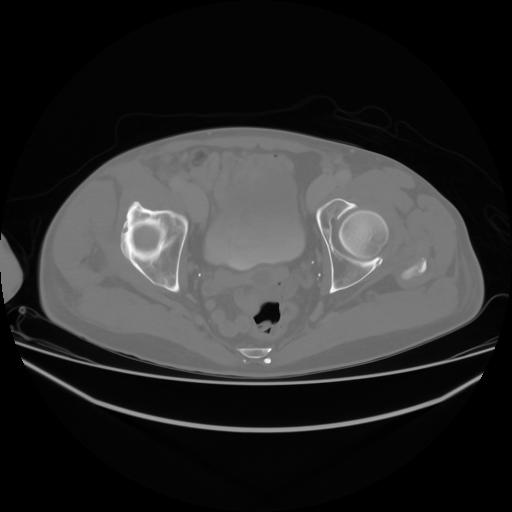

4 CUERPO,CE,Axial,3.0,CUERPO,,